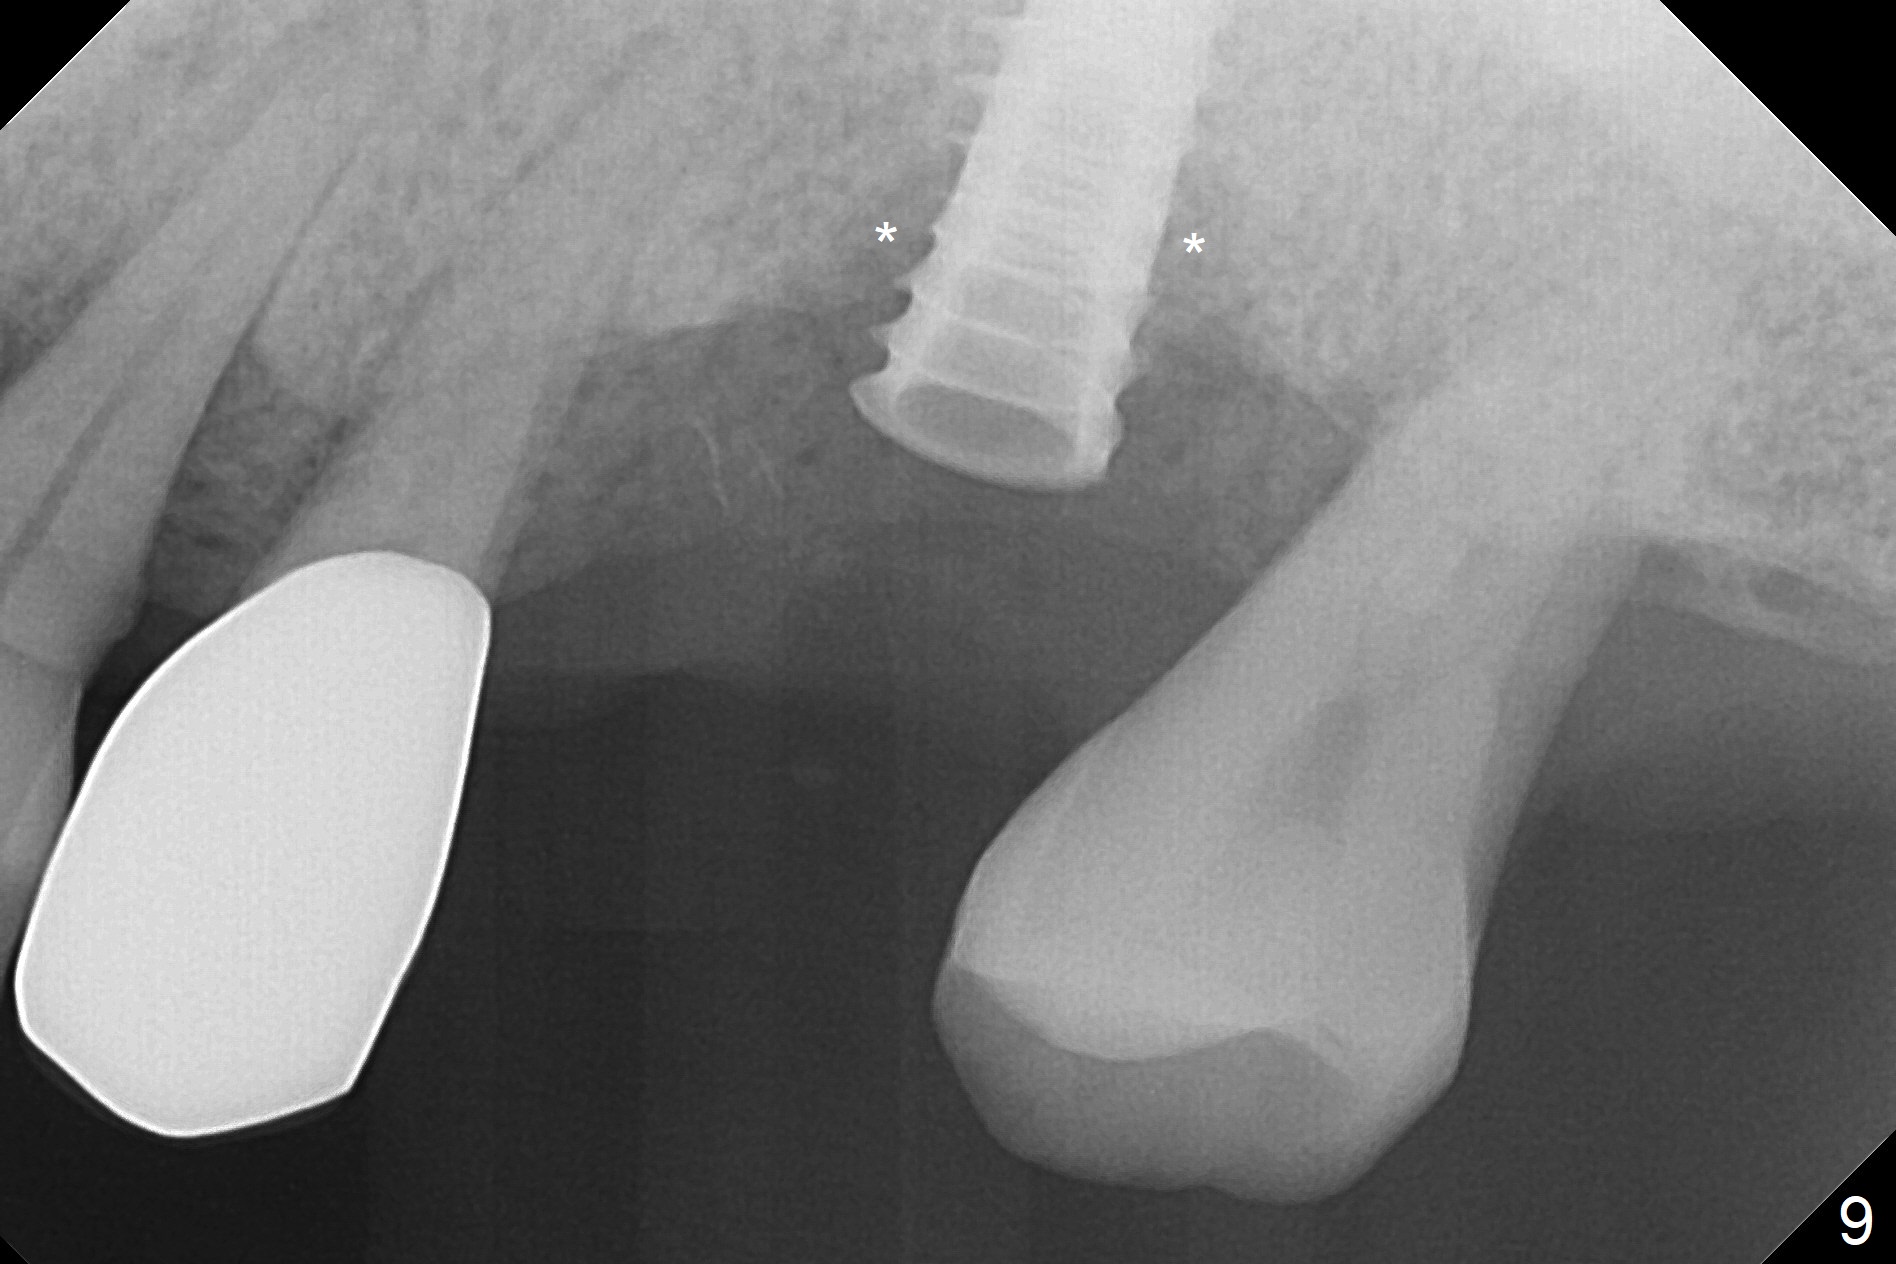

The amount of the bone graft mesial and distal the implant seems to reduce 3 and 4 months postop, respectively (Fig.6,7 arrowheads). When the acrylic is cut off 4 months postop, the bone graft is loose. The gingiva is unhealthy. The abutment and implant are loose. A healing abutment is placed (5x4 mm). The implant is torqued to 35 Ncm 6 months postop with the healing abutment reapplied. The patient will return for follow up nearly 9 months postop. A larger healing abutment will be used if the implant is stable. Two weeks later, use a smaller restorative abutment for easy impression. In fact the implant is unstable with #15 mesial shift due to abnormal occlusion with #17 (Fig.8). Bone density around the implant is low (* in Fig.9 (PA), 10,11 (CT sagittal, coronal sections)). A healing screw is placed for self healing. A 2nd option is to remove the implant (Fig.12), BEB (Fig.13) and place the implant deeper (Fig.14) or larger one (5.5-6.5x13 mm). The 3rd option is to place larger and longer implants (Fig.15 (tapered), 16 (cylindrical)). The implant access has partially closed 14 months postop, but there is a small buccal opening with sanguine exudate. Incision reveals severe bone loss around the implant; the mobile tooth #15 is extracted (Fig.17). After debridement and irrigation with normal saline, Vera Graft (Fig.18 *) and Collagen plug are placed with periodontal dressing.